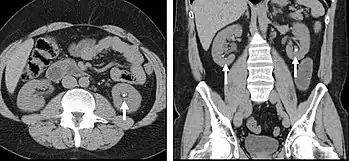

FIGURE 1. Non-contrast CT demonstrating multiple bilateral renal calculi (arrows), which can be obscured on contrast-enhanced images, particularly delayed images when there is excreted contrast in the renal collecting system; axial left, coronal reformat on right.

Non-contrast CT scans Figure 1a (left) and 1b (right) are of limited use for the differentiation of soft tissue structures. However, materials like blood, calcium (renal stones, vascular atherosclerosis), bone, and pulmonary parenchyma are highly visible and can usually be adequately assessed with non-contrast CT. For example, in the abdomen and pelvis, there are several indications for non-contrast imaging. These include: evaluation of renal calculi; assessment for gross intra-abdominal hemorrhage; and post-endostent volume measurements. In addition, non-contrast images are often obtained in conjunction with contrast enhanced images in evaluating potential renal transplant donors and in the evaluation of the pancreas (in combination with contrast phases). Of note, dual-energy CT and the development of virtual “non-contrast” images may ultimately obviate the combination scans. Additionally, CT angiography examinations performed for pathologies like aneurysms and dissection are frequently performed in conjunction with non-contrast imaging. The non-contrast images facilitate the differentiation of active extravasation or acute bleeding from vascular calcifications.